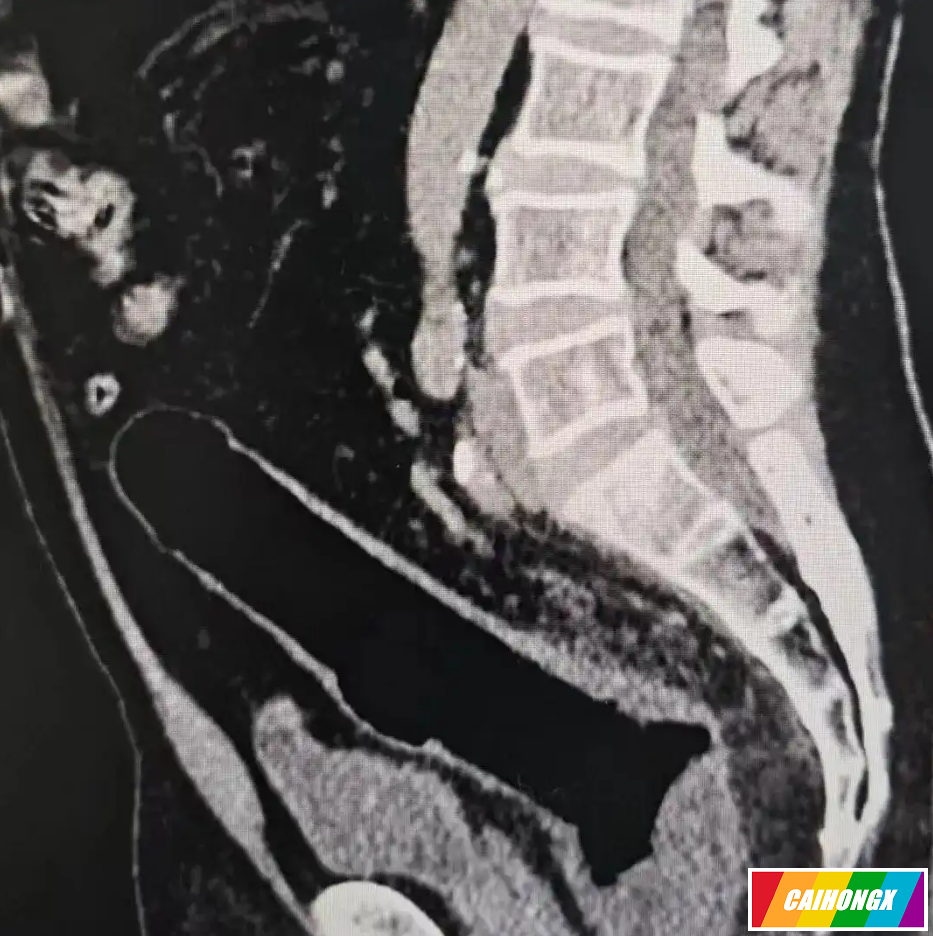

CT检查结果让医生大吃一惊:肠道已严重穿孔,腹腔内充满脓液,感染扩散明显。原本简单的异物取出,瞬间升级为危及生命的急症。医生立即安排紧急手术,成功取出异物,但由于肠道损伤严重,患者不得不先接受肠道造口手术(俗称“人工肛门”),把肠管拉出体外临时排便。